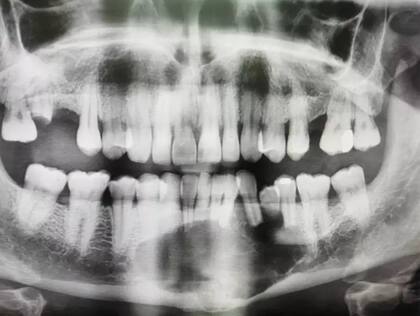

"Le tenía tanto miedo al dentista que no había ido en 27 años. Tenía una radiografía que mostraba una sombra masiva, un agujero negro en el medio de la cara y el dentista dijo que nunca había visto algo así antes", explica al Daily Mail su esposa Mel quien vive junto al hombre en Sheffield, Inglaterra.

Luego que el dentista encuentre la preocupante sombra en la radiografía, Darren fue derivado como un caso no urgente al Hospital Charles Clifford Dental en Sheffield. Después de dos biopsias, se confirmó que se trataba de un 'tumor grande y localmente agresivo' llamado ameloblastoma que debía extirparse lo antes posible.